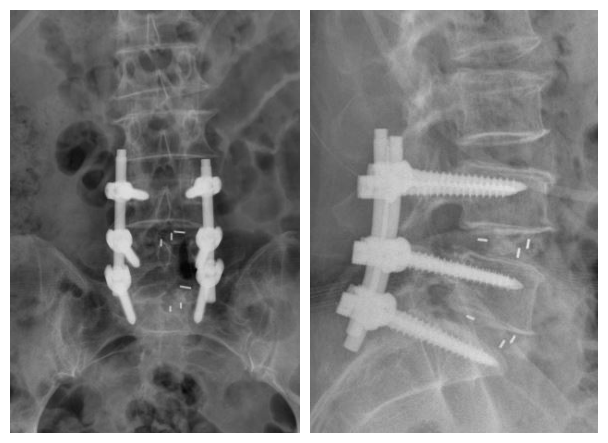

张宏主任亲自主刀,手术顺利。患者术后5天疼痛消失下床活动:

老年人腰椎疾病很多,大部分人保守治疗是有效的,但是有些老人就不得不靠手术解决问题。老人和家属普遍担心腰椎做手术会瘫痪,总是希望一根针解决所有问题,提到手术就放弃,结果往往延误治疗。

实际上腰椎手术是很安全的,误伤神经的事情已经极其罕见。经过这些年的技术发展,腰椎手术的创伤已经比10年前小得多,而我们骨科二病区新开展的腰椎通道下融合手术,可以进一步减少创伤,减少出血,缩短康复时间。对于保守治疗解决不了疼痛的老人,是个很好的选择。